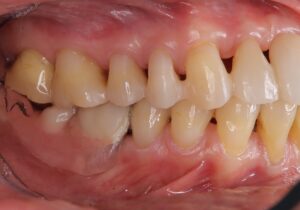

治療前 下顎両側大臼歯欠損は放置され、上下顎前歯は前方に傾斜・突出した状態であり、上顎の右側中切歯は動揺が著明で、全顎的に歯肉の発赤・腫脹がありました。

治療後 上下顎両側大臼歯欠損は目立たない部分入れ歯が装着され、上下顎前歯の前方への傾斜・突出と隙間の改善を認めます。、全顎的な歯肉の発赤・腫脹も改善されています。

3. 下顎部分入れ歯を装着しながらの歯列矯正処置

歯周病患者さんであるため、ワイヤーを用いた歯列矯正処置(マウスピース矯正では歯が揺れてしまうため)を9ヶ月行い、歯の病的な位置異常を是正して、見た目とともに機能の改善を図りました。部分入れ歯の設計を考慮して歯列矯正処置を行うとともに、奥歯での噛み合わせを確保しています。